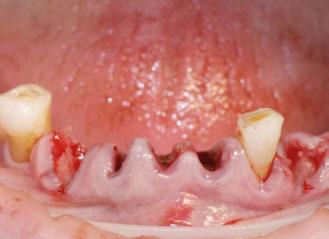

Exploración Intraoral

Presenta un estado oral deficitario. Parcialmente edéntula, con colapso de mordida, migración dental patológica, restauraciones de resina antiguas fisuradas y filtradas, transparencia y exposición de cámara pulpar secundaria a desgastes con pérdida de estructura e integridad de tejido dental importante (Figuras 1 a 4). Portadora a tiempo parcial de prótesis removibles desadaptadas de más de 10 años de antigüedad, refiriendo incapacidad de adaptación a este tipo de prótesis.

Exploración radiológica

Mediante CBCT constatamos atrofias óseas severas y disminución de soporte óseo periodontal en relación con las piezas dentales.